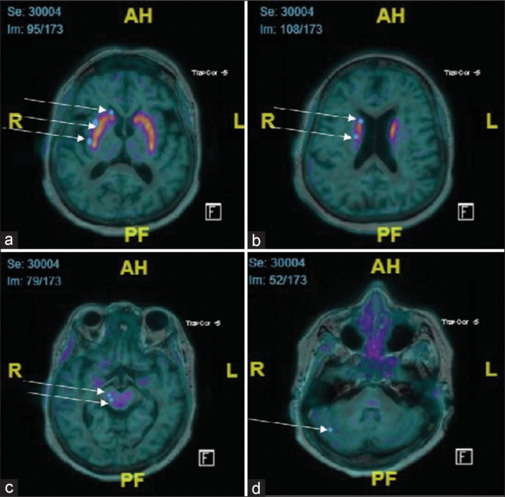

Materials and methods: Sixty patients referred from neuropsychiatric outpatient department were retrospectively analyzed who underwent (18F)-DOPA magnetic resonance (MR)-PET scans. Out of 60 subjects, 36 were diagnosed with IPD, 5 were cases of other movement disorders, and 19 were normal on PET imaging (NDDS). To evaluate and quantify the tracer uptake from the PET scans, a region of interest (ROI) was drawn on the least radiotracer uptake region, and subsequently, on bilateral occipital cortex, caudate (head, body, tail), putamen (anterior, posterior), periaqueductal gray matter and red nucleus using structural MR images (MRI) for better delineation of anatomical regions. Tracer uptake ratios from each selected region were generated as SUVmax of ROI/occipital. The statistical analysis was performed using SPSS 29.0 version.

Results: The posterior putamen showed a significant difference between IPD and other patients with an SUV cutoff of 1.69 and 100% specificity and 99.2% accuracy for normal controls. Whereas, we observed an SUV cutoff of 1.75 and an accuracy and specificity of 100% in patients with other movement disorders. The absolute values from the caudate nucleus were demonstrating a statistical significance between other movement disorders compared to normal controls with a cutoff of 1.69 and an accuracy of 81.2%. The ratio of posterior putamen/occipital ratio was significant between IPD and normal controls, with a cutoff of 3.89 and an accuracy of 95.6%. Right caudate to occipital ratio (RCOR) was significant for differentiating between other movement disorders and normal controls with a cutoff of 3.01 and an accuracy of 95.6%. One novel finding was that occipital lobe uptake was significantly reduced in patients with IPD compared to other movement disorders.